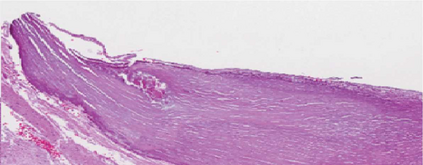

Coronary artery disease (CAD) is a cardiovascular condition with high morbidity and mortality. Intravascular optical coherence tomography (IVOCT) has been considered as an optimal imagining system for the diagnosis and treatment of CAD. Constrained by Nyquist theorem, dense sampling in IVOCT attains high resolving power to delineate cellular structures/ features. There is a trade-off between high spatial resolution and fast scanning rate for coronary imaging. In this paper, we propose a viable spectral-spatial acquisition method that down-scales the sampling process in both spectral and spatial domain while maintaining high quality in image reconstruction. The down-scaling schedule boosts data acquisition speed without any hardware modifications. Additionally, we propose a unified multi-scale reconstruction framework, namely Multiscale- Spectral-Spatial-Magnification Network (MSSMN), to resolve highly down-scaled (compressed) OCT images with flexible magnification factors. We incorporate the proposed methods into Spectral Domain OCT (SD-OCT) imaging of human coronary samples with clinical features such as stent and calcified lesions. Our experimental results demonstrate that spectral-spatial downscaled data can be better reconstructed than data that is downscaled solely in either spectral or spatial domain. Moreover, we observe better reconstruction performance using MSSMN than using existing reconstruction methods. Our acquisition method and multi-scale reconstruction framework, in combination, may allow faster SD-OCT inspection with high resolution during coronary intervention.